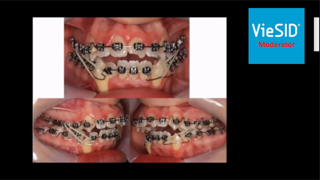

左下が今回のプレゼンテーション症例、右下が当院で行われた矯正治療症例です。

まず、先生の提示されたケースにおいては通法通り矯正器具とゴムによる牽引で前歯が閉鎖されているのが分かりますね。

矯正治療には「顎間ゴム」という弾性ゴムを装着するのがスタンダードになります。

上下の歯にゴムを付ける事(診断によってゴム位置は変わります)で顎を閉じさせる効果があります。